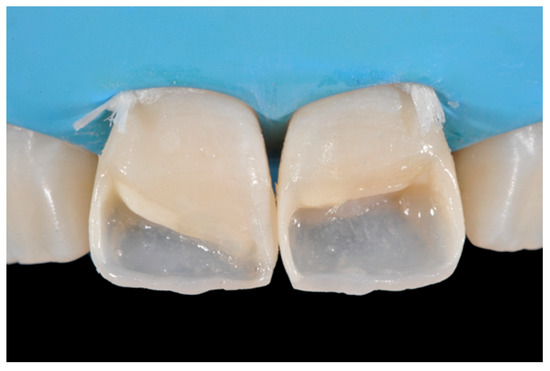

A wise balance of these opaque and translucent shades represents the key factor in obtaining reliable esthetic outcomes and great attention should be paid for their correct positioning [10,27]. Nevertheless, it happens that, during the restorative procedures, some inaccuracies could be made resulting in having opaque shades in place of translucent ones. This is generally realized too late, after finishing and polishing procedures thus compromising the final esthetic result [25]. In Figure 58 in fact the esthetic outcome of the left central incisor could have been improved if the opaque incisal margin had been made thicker and festooned. Conversely, we can notice from Figure 59 excessive thickness in the opaque incisal margin that, if not reduced, could provide an unpleasant final esthetic result.

Figure 58.

A more accurate management of the frame could have improved the thin and not festooned incisal opaque margin on left central incisor.

Figure 59.

Completing the restorations without previously reducing the incisal frame could provide an unpleasant final esthetic outcome.